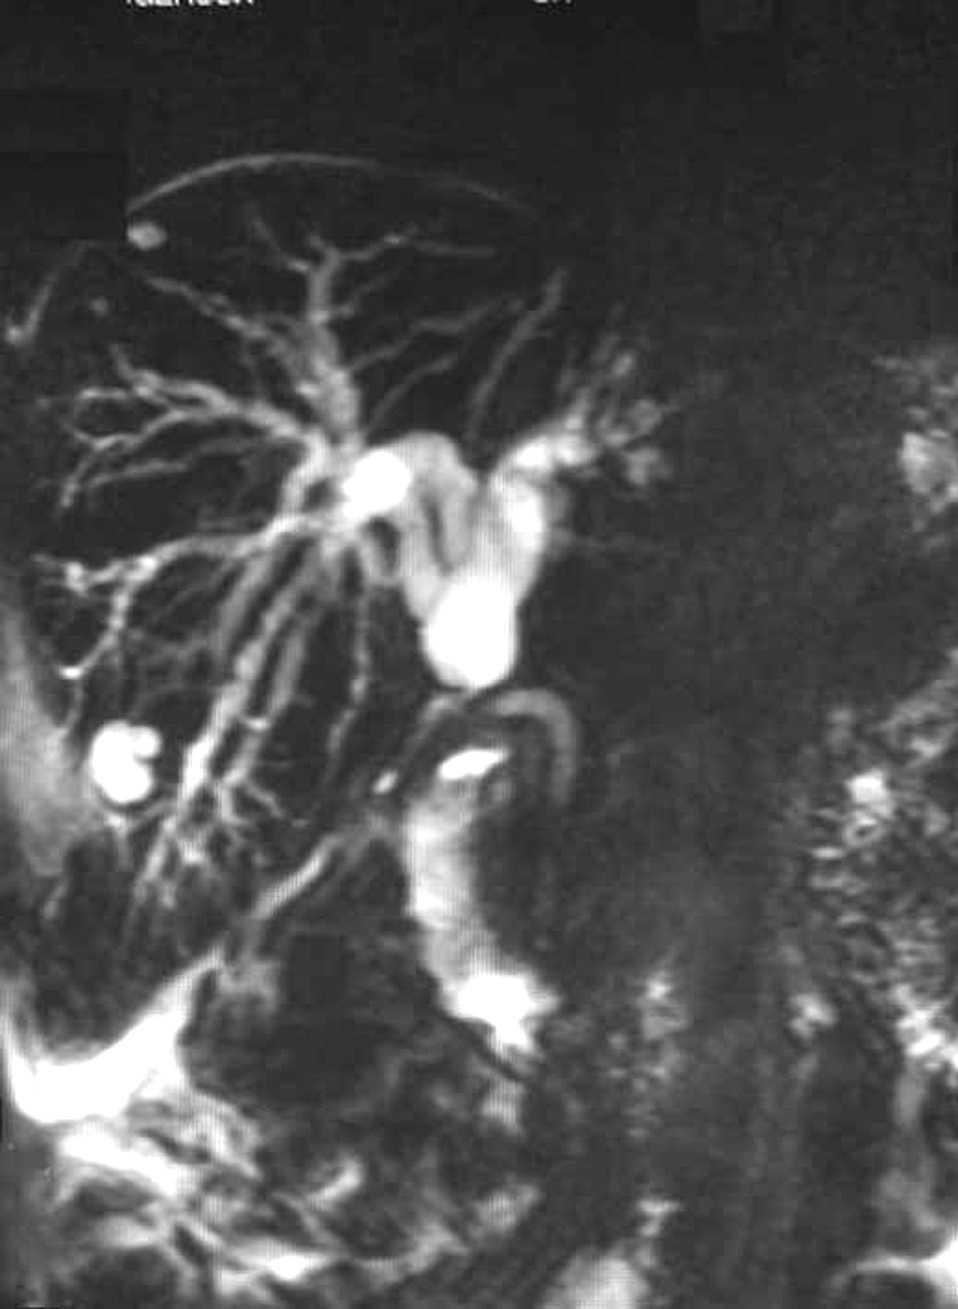

Fig. 1.

Varón de 40 años con antecedentes de cirugía laparoscópica en abril 2002 (intervención de Toupet y colecistectomía por colelitiasis). Acudió a urgencias en octubre de 2002 por un cuadro de fiebre, escalofríos e ictericia con coluria y prurito generalizado. En la exploración el paciente mostraba ictericia cutaneomucosa y dolor en el hipocondrio derecho a la palpación profunda, sin signos de irritación peritoneal. El estudio analítico demostró un patrón de colostasis (Bi 7,4 mg/dl, AST 299 U/l, ALT 525 U/l, FA 772 U/l, GGT 1141 U/l) y CA 19,9 144,51 U/ml. La colangiopancreatografía retrógrada endoscópica (CPRE) reveló una estenosis en la unión del conducto hepático común con los conductos hepáticos en probable relación con cirugía previa. La colangiografía por resonancia magnética (CRM) (figs. 1 y 2) mostró una estenosis importante en hepático común con dilatación de vía biliar intrahepática. En el interior de la vía biliar, por encima de la estenosis, se identificó una imagen de densidad disminuida, en probable relación con una coledocolitiasis. En la intervención quirúrgica se evidenció una estenosis de la vía biliar en la confluencia de los conductos hepáticos. Se realizó resección de la zona estenótica y hepaticoyeyunostomía en “Y” de Roux terminolateral transmesocólica. En el interior de la vía biliar se objetivó un endoclip embebido en una litiasis pigmentada (fig. 3). La anatomía patológica informó de segmento de vía biliar con una luz de 4 mm de diámetro, ausencia de epitelio y un infiltrado inflamatorio crónico y fibrosis de la pared. No había signos de malignidad. El postoperatorio transcurrió sin incidencias.